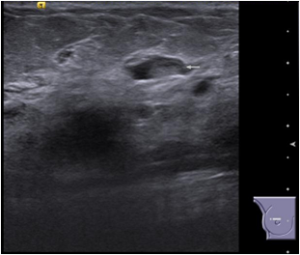

Bilateral Mammograms revealed increased reticular densities in the upper half of the right breast. A 16 mm well defined nodule seen in the left subareolar region. BIRADS 3/4 Bilateral breast ultrasound revealed extensively dilated ducts showing thickened walls and intra ductal contents corresponding to the increased reticular densities on the mammogram of right breast. Left breast revealed a 17 x 10 mm well defined low echogenic lesion with posterior enhancement in the left subareolar region. BIRADS 3 MRI showed segmental clumped / clustered ring enhancement extending from 10 to 2 O’ clock position in the right breast with extensive ductal branching and intraluminal contents extending till the nipple suspicious for DCIS. Left breast revealed a benign 16 x 14mm well defined nodule in the lower inner quadrant close to the nipple. BI-RADS-4.